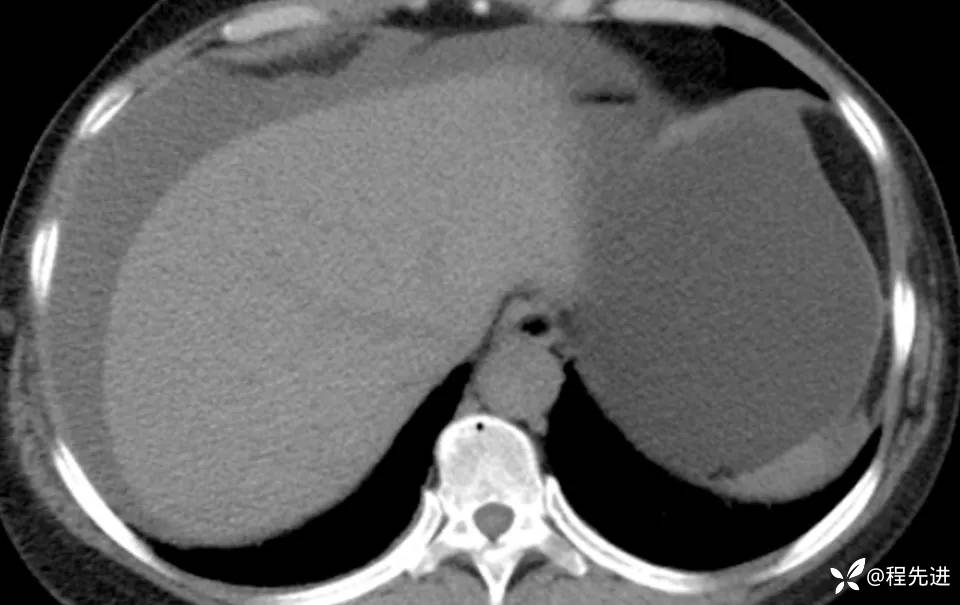

患者性别:女

患者年龄:56岁

简要病史:腹胀伴劳累性胸闷1月

肿标:CA125: 546.99U/ml;CA199: 269.9 U/ml,余未见异常

CT平扫+增强: